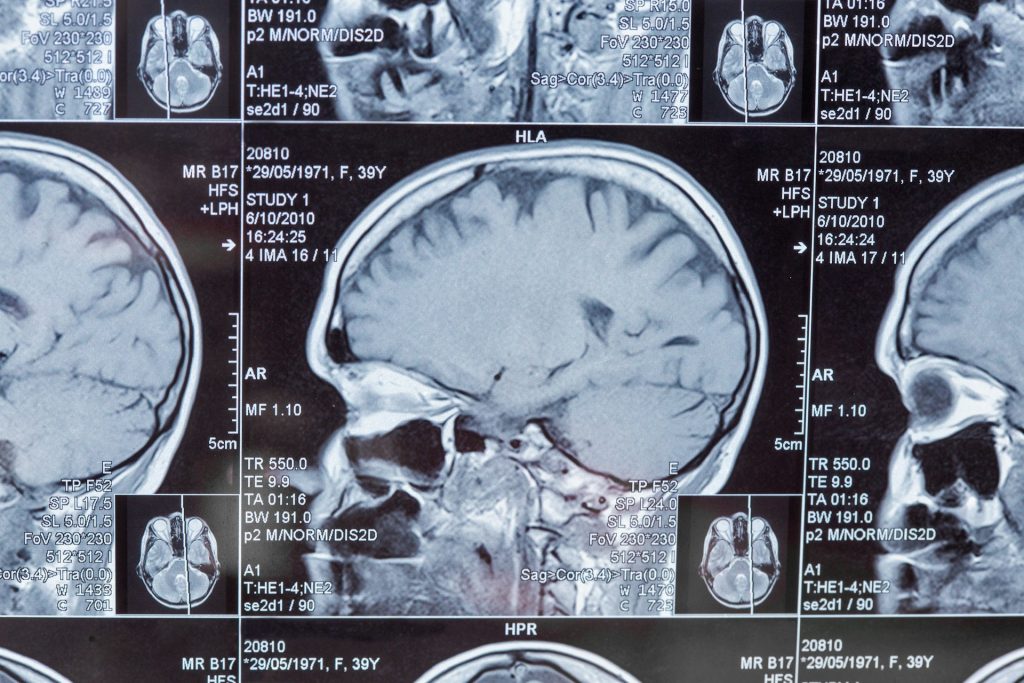

Why dementia symptoms often go undiagnosed for years

'Just getting older' is often the explanation given when someone forgets things—but new research suggests these assumptions may be masking something more serious: undiagnosed dementia.

Brain injuries may cause dementia in older people

knowridge.com - 08/Oct 14:14

A new study has found that older adults who suffer a traumatic brain injury (TBI) are more likely to develop dementia, need home care, or be admitted...